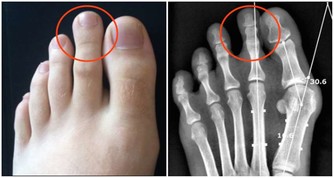

4、捏腳踝

腳踝分佈著淋巴管、血管、神經等重要組織,是腳部與人體血液流動的重要關口,流經靜脈回心血液。

當心臟不能好好工作時,靜脈血液不能順利回流,引起靜脈內壓力升高,體液漏出進入組織間隙,表現為下肢水腫,尤其是腳踝水腫症狀。

檢測方法是:手指按壓腳踝或小腿,手指鬆開後按壓部位呈凹陷狀,通常不能立即恢復。出現這種情況時,須及時就醫做下肢超聲檢查。

建議每天不妨抽點時間做做踝關節運動,以促進全身的血液循環,增加回心血量,保護心臟。具體方法是:

(1)站立旋踝,一腳站立,另一隻腳旋轉畫圈,雙腳交替進行,每次10分鐘左右。

(2)交替踮腳,兩腳腳尖前1/3腳掌著地,其餘2/3懸空站立,踮起腳尖,放下,重複20次。

需要注意的是,活動腳踝時切忌用力過大、過猛,以防踝關節軟組織損傷。